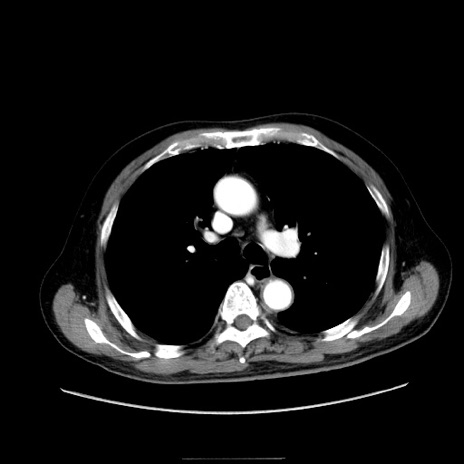

症例30(横断像)

【症例】80歳代男性

【主訴】臍周囲痛

【現病歴】約6時間前から臍下部痛が出現。次第に腹部膨隆・背部痛も生じてきたため来院。背部痛の場所は変化しない。

【身体所見】意識清明、BT 36.3℃、BP  131/87mmHg、P 87bpm、SpO2 100%(RA)、臍周囲自発痛・圧痛あり、反跳痛なし、自発痛部位に一致して板状硬あり、腹部膨隆、腸雑音減弱、CVA tenderness両側陰性。

【データ】WBC 19600、CRP 0.33